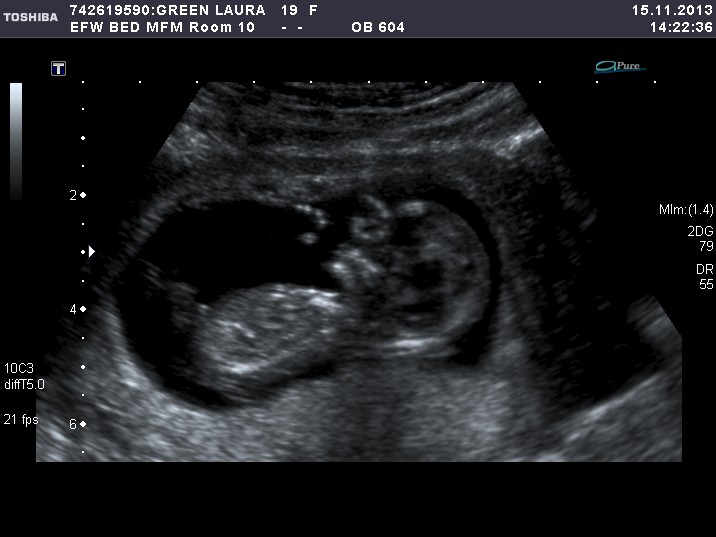

First time posting and I'm not sure if the pics uploaded properly. These are three pics from the 12 week ultrasound. Any ideas if its a boy or girl? Thanks for your help!